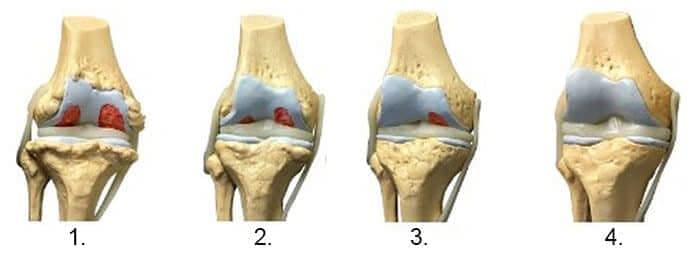

1. Nedostatek živin v kloubu. Dochází k narušení chrupavkové tkáně. 2. Obnovení chrupavkové tkáně v kloubu během 2 týdnů díky gel Depanten . 3. Obnovení chrupavkové tkáně v kloubu během 3 týdnů díky Depanten . 4. Zdravý kloub po dokončení kúry s gel Depanten .

— Na obrázku níže vidíte typický proces obnovy chrupavkového kloubu.